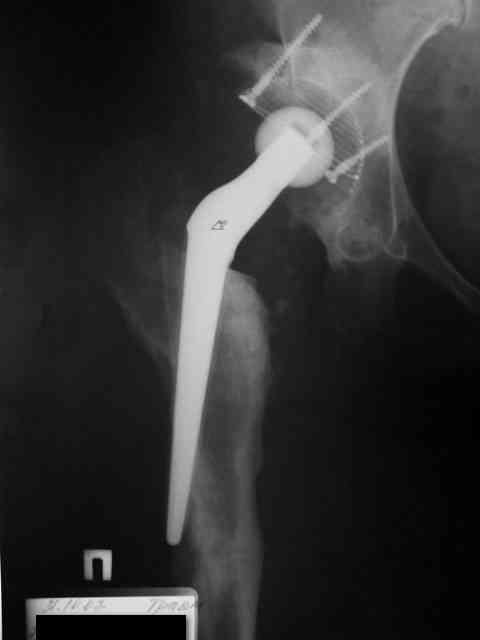

Эндопротез - нестабильность

Здравствуйте, уважаемые коллеги!Прошу совета дальнейшей тактики лечения-нужна ли операция,

и если нужна в какие сроки. R-снимок в приложении.